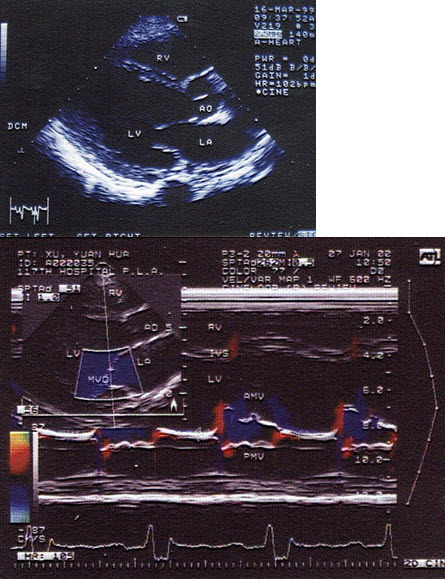

30、单项选择题

根据心尖四腔切面声像图所示,超声诊断为()

A.右房血栓

B.三尖瓣赘生物

C.右房黏液瘤

D.正常声像图

E.二尖瓣脱垂